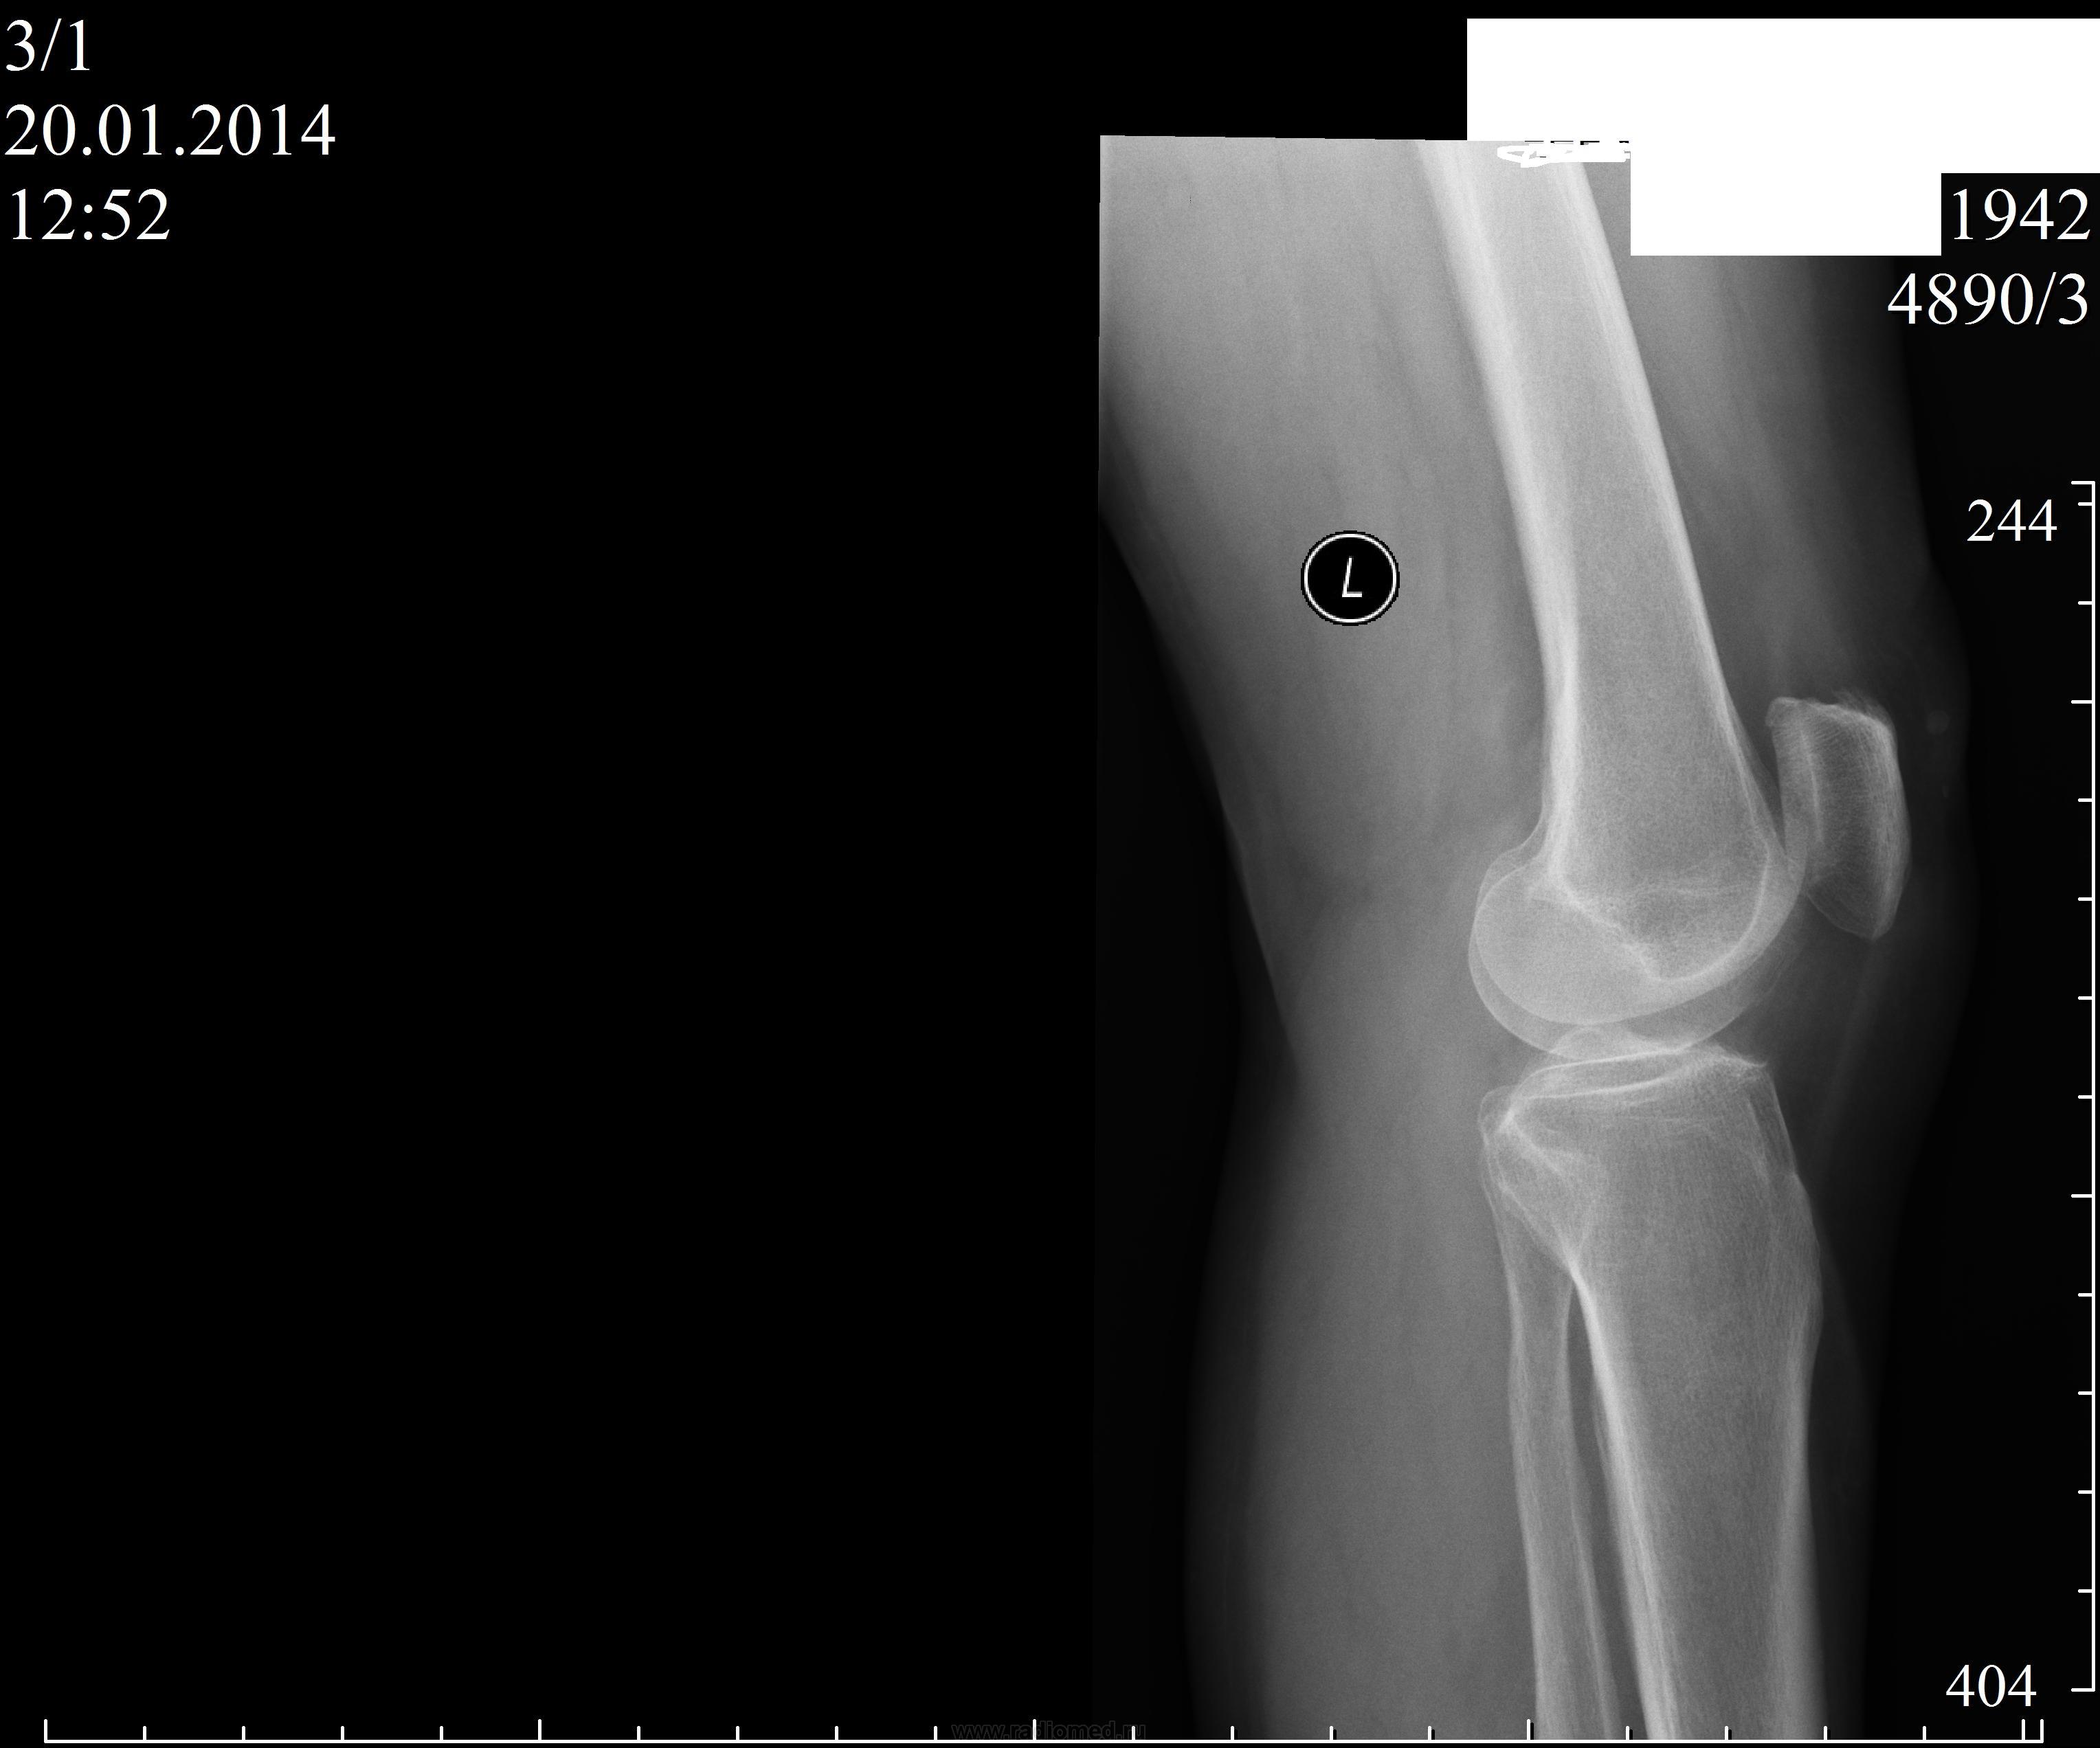

Пол пациента: Женский пол Тип патологии: Доброкачественное новообразование, киста Область исследования: Скелетно-мышечная система Методы исследования: Rg Пациентка 72 года .Жалобы на боли в области коленных суставов.Интересует как надо расценивать, обызвествление в эпиметафизе правой бедренной кости? https://radiomed.ru/sites/default/files/styles/case_slider_image/public/user/406/koleni2.jpg?itok=m3Q9oVz_ https://radiomed.ru/sites/default/files/styles/case_slider_image/public/user/406/koleni4.jpg?itok=k4rvytcG ID:34952 Пнд, 20/01/2014 - 16:46 #1 Almo Не на сайте Был на сайте: 11 часов 59 минут назад Зарегистрирован: 28.09.2008 - 18:50 Публикации: 8304 Больше интересует дальнейшая тактика? Пнд, 20/01/2014 - 17:51 #2 maker4ik Не на сайте Был на сайте: 9 лет 1 день назад Зарегистрирован: 19.10.2011 - 17:49 Публикации: 2682 Инфаркт костного мозга? Пнд, 20/01/2014 - 18:16 #3 Almo Не на сайте Был на сайте: 11 часов 59 минут назад Зарегистрирован: 28.09.2008 - 18:50 Публикации: 8304 Может быть, но как быть уверенным? Пнд, 20/01/2014 - 19:07 #4 Dima Не на сайте Был на сайте: 7 лет 7 месяцев назад Зарегистрирован: 05.08.2012 - 17:39 Публикации: 2467 Мне кажется что все таки больше данных за неопластический процесс, энхондрома как вариант. Терпимость - это когда прощают чужие ошибки; такт - когда не замечают их. (Артур Шницлер) Пнд, 20/01/2014 - 20:23 #5 Андрей Юрьевич Не на сайте Был на сайте: 2 недели 3 дня назад Зарегистрирован: 16.11.2008 - 22:16 Публикации: 18106 Все уже не так просто. Читайте http://www.radiologyassistant.nl/en/p4bc9a97980036/sclerotic-bone-tumors-and-tumor-like-lesions.html , диференцируйте. Андрей Юрьевич Пнд, 20/01/2014 - 22:31 #6 алкс Не на сайте Был на сайте: 10 лет 5 месяцев назад Зарегистрирован: 24.10.2012 - 22:55 Публикации: 2915 Dima wrote: Мне кажется что все таки больше данных за неопластический процесс, энхондрома как вариант. Ну в 72г. скорее инфаркт м.б. чем нео, и вариант Ср, 22/01/2014 - 17:30 #7 ren_gen Не на сайте Был на сайте: 11 лет 6 месяцев назад Зарегистрирован: 30.10.2010 - 19:17 Публикации: 285 энходрома, диф. с вторичной хондросаркомой, менее вероятен инфаркт (картинка не совсем похожа) биопсия поставит точку

Мне кажется что все таки больше данных за неопластический процесс, энхондрома как вариант.

Ну в 72г. скорее инфаркт м.б. чем нео, и вариант

энходрома, диф. с вторичной хондросаркомой, менее вероятен инфаркт (картинка не совсем похожа)

биопсия поставит точку